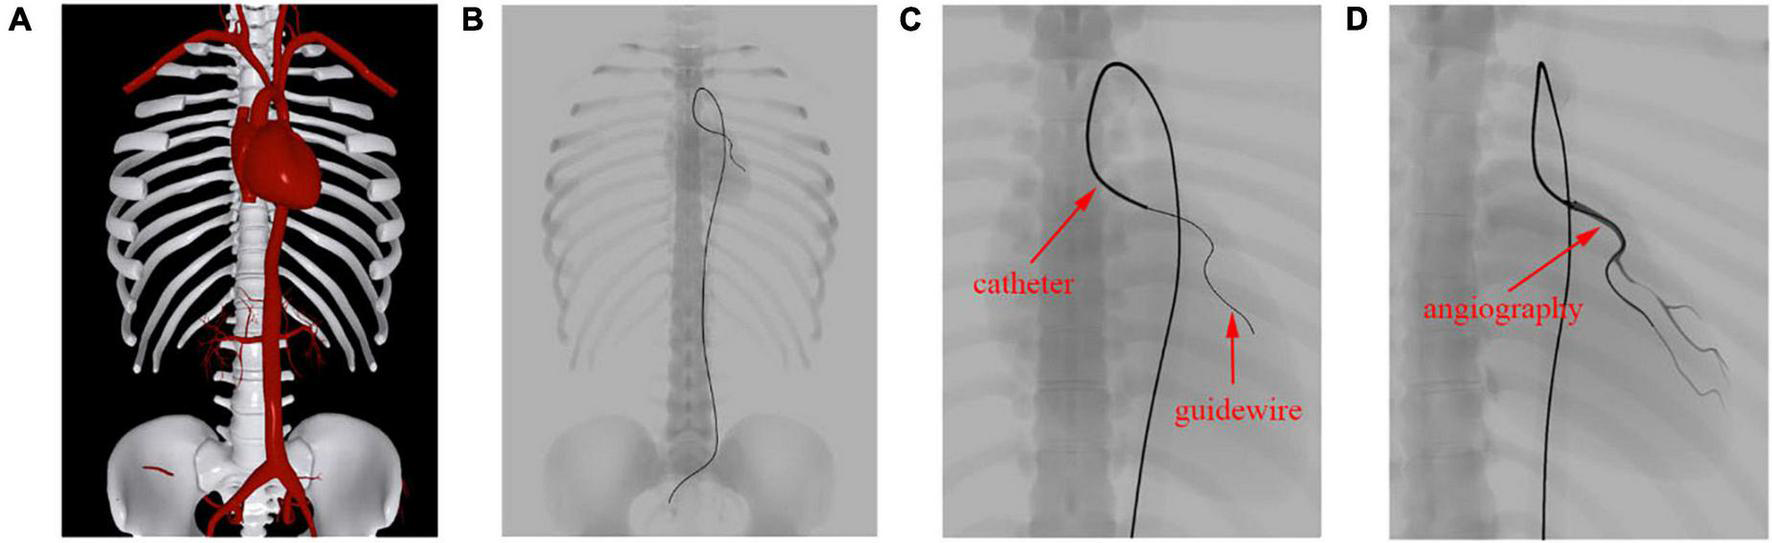

In this experiment, a cardiac training case is imported into our simulator. The imported meshes contain a skeleton, vessel, and heart. The devices used in this procedure are a catheter and guidewire. The anatomy rendered in the Phong lighting model is displayed in Figure 10A. The corresponding simulated fluoroscopic image is shown in Figure 10B. We move the virtual camera closer to the devices and take a screenshot, which is shown in Figure 10C. Then, angiography is simulated, and the enhanced coronary artery vessels are displayed in Figure 10D.

FIGURE 10

Simulation results of fluoroscope imaging. (A) Anatomy rendered in the Phong lighting model. (B) Anatomy and surgical devices under a simulated fluoroscope. (C) Zoomed view of the devices in the left coronary artery. (D) Contrast-enhanced coronary artery vessels.

The skeleton, vessels, and heart mesh can be clearly seen in Figure 10A, while only the skeleton can be identified in Figure 10B. This is because the skeleton’s attenuation in X-ray is much higher than that of the vessels. Unlike human anatomy, surgical devices can be easily found under the fluoroscope because of their specialized materials. The catheter is a hollow tube device with a larger diameter than that of the guidewire, and it can be treated as solid. Thus, we can distinguish these devices by the width of the centerline in Figure 10C. After contrast medium is injected through the catheter, the affected vessel branches are visualized in a dark color under the fluoroscope, as shown in Figure 10D. The frame rate remains at 60 fps regardless of whether the fluoroscope effect is enabled. These results demonstrate that our algorithm can efficiently simulate the X-ray imaging effect of objects with varying properties by tuning the weight value s as explained in section “Fluoroscopy Simulation.”